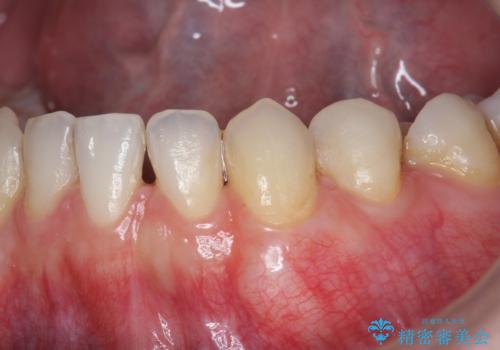

総合歯科治療 → 歯周病治療&矯正歯科治療

- クロスバイト・歯並びが原因の歯肉退縮歯、矯正治療による審美性の改善

- 歯茎の下がりが気になる 歯肉移植でさがりにくくする- 担当医 井上季実子